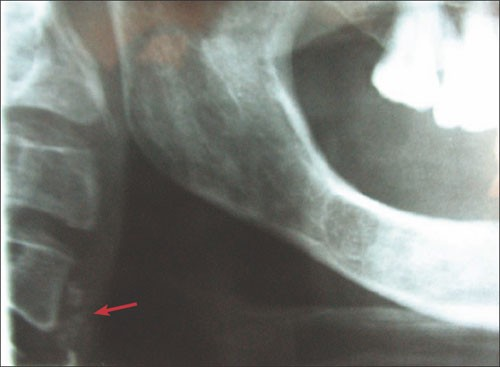

3. What condition can be seen in the following X ray?